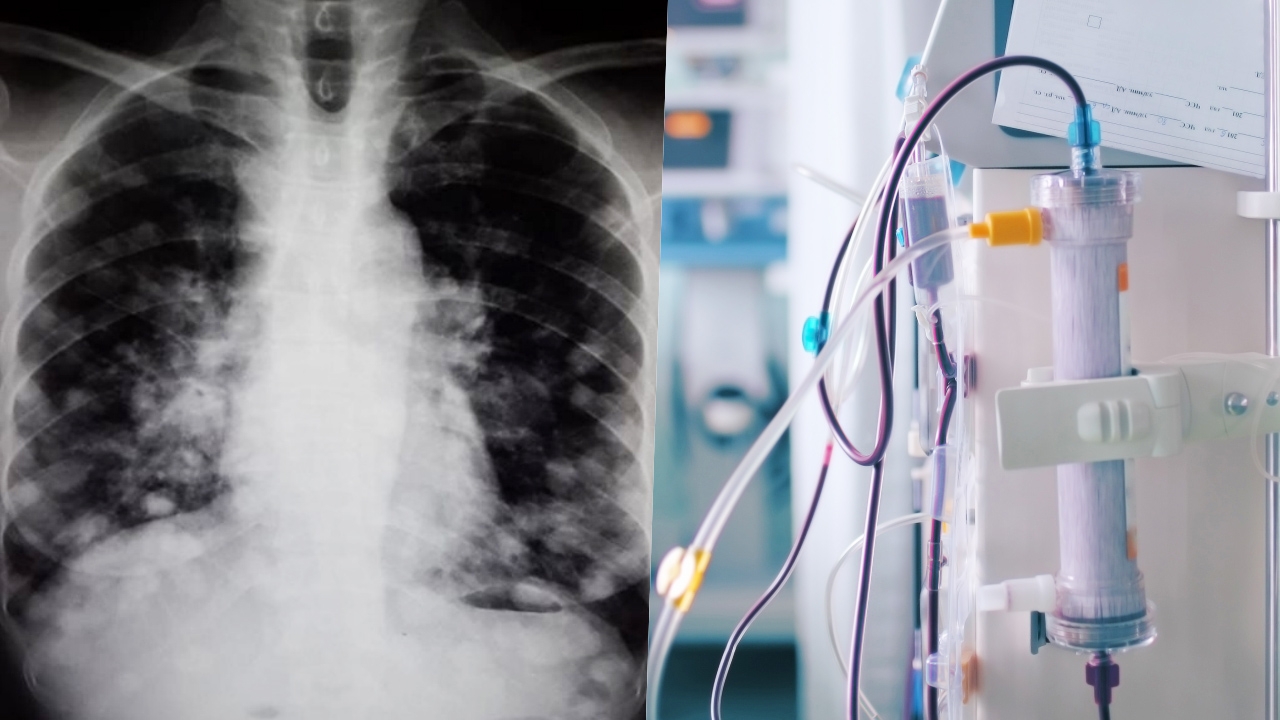

แฟนเพจเฟซบุ๊ก นพ.สุภัทร ฮาสุวรรณกิจ โพสต์ภาพและข้อความระบุว่า ภาพนี้เราจะเห็นจุดสีขาวกระจายไปทั่วในทรวงอกและเนื้อปอดสีดำ ปกติปอดจะมีอากาศเป็นองค์ประกอบหลัก แสงเอกซเรย์ทะลุผ่านได้ไปกระทบแผ่นฟิล์มได้จึงเห็นเป็นสีดำ

หากมีก้อนเนื้อหรือน้ำ แสงเอกซเรย์จะทะลุทะลวงไปกระทบฟิล์มเอกซเรย์ได้น้อยกว่าจึงเห็นเป็นสีขาว ภาพนี้ชัดเจนว่า มีก้อนขาวๆ กลมๆ รีๆ กระจายทั่วปอดไปหมด นี่คือ มะเร็งระยะสุดท้ายที่กำลังลุกลาม